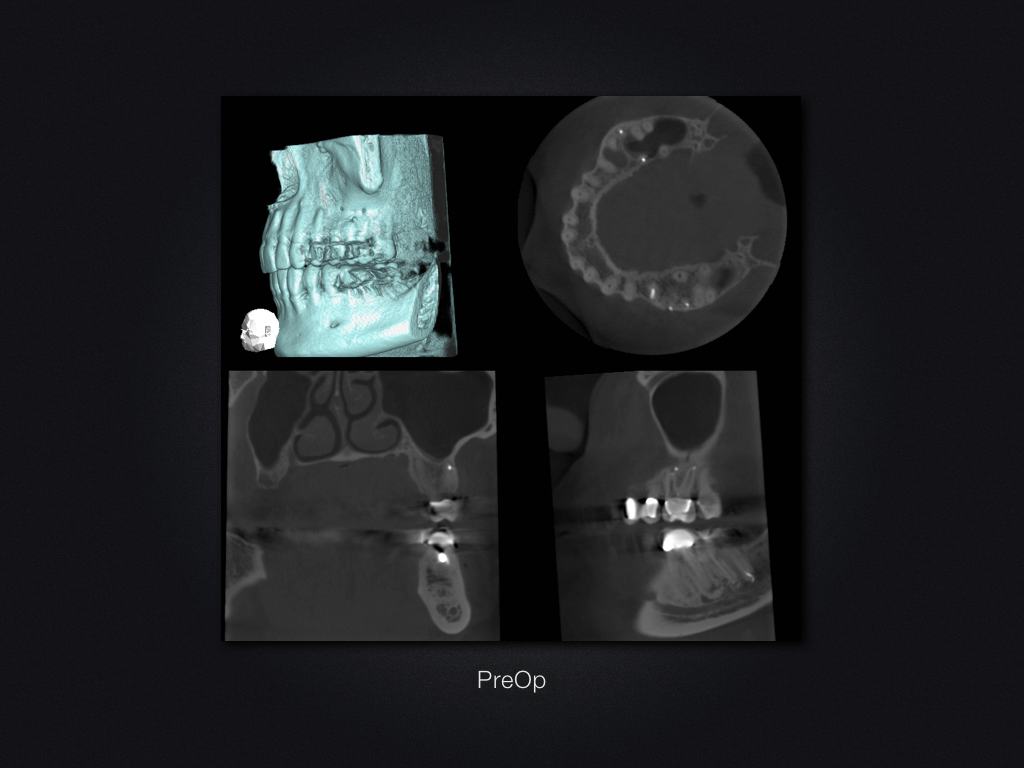

26D.005

2D vs. 3D (XXVI)